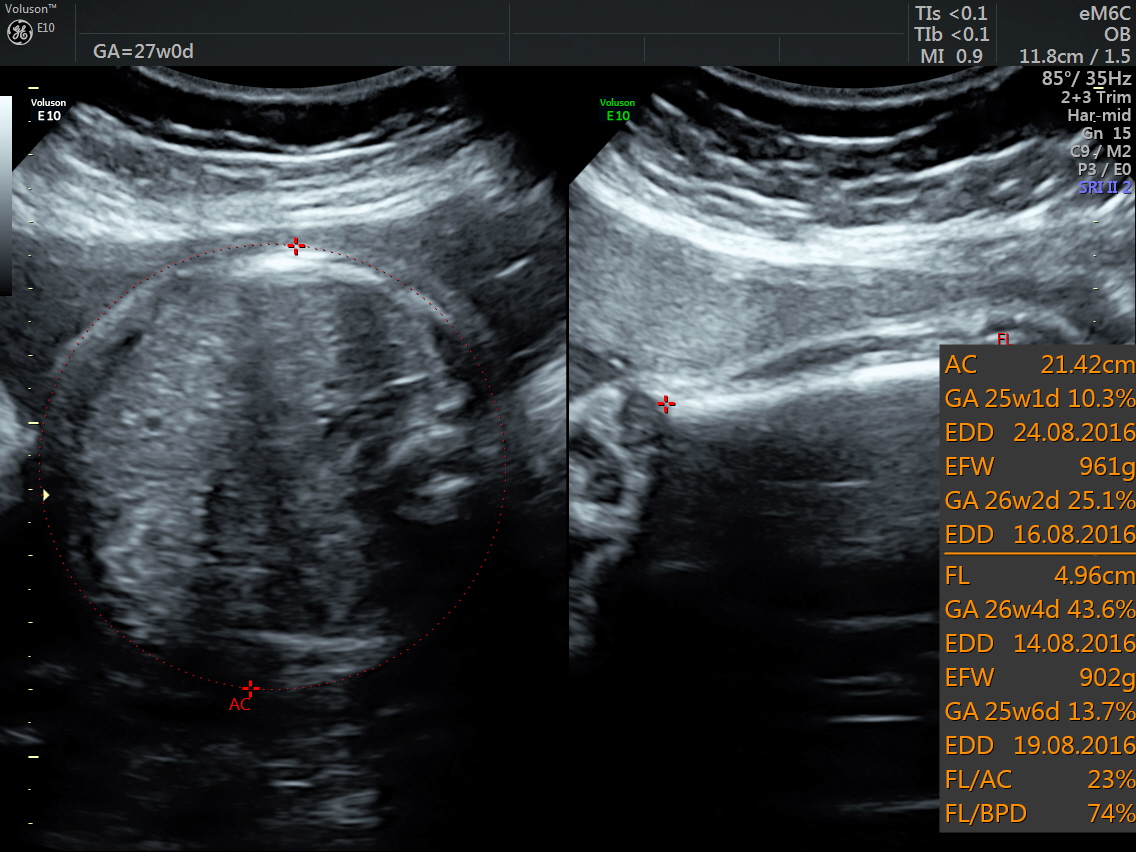

RT AORTIC ARCH_28 Published June 17, 2016 at 1136 × 852 in Rt aortic arch and aberrant left subclavian artery ← Previous Next →